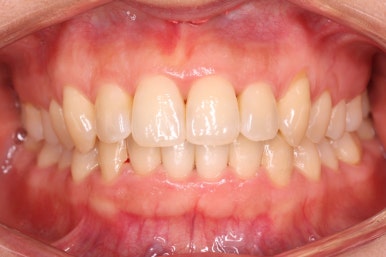

부산설측교정 키다리아저씨치과에서 부분교정을 마무리 하였습니다.

장치를 모두 제거하고 유지철사를 안쪽으로 부착하고 치료를 종료하였습니다.

전후사진을 비교해 보겠습니다.

삐뚤었던 부위들은 가지런하게 정리가 되었습니다.

부분교정이기 때문에 입술을 다물고 계실 때의 입매나 느낌은 거의 변화가 없고, 웃거나 말할 때 드러나는 치아의 느낌은 매우 좋아졌습니다.